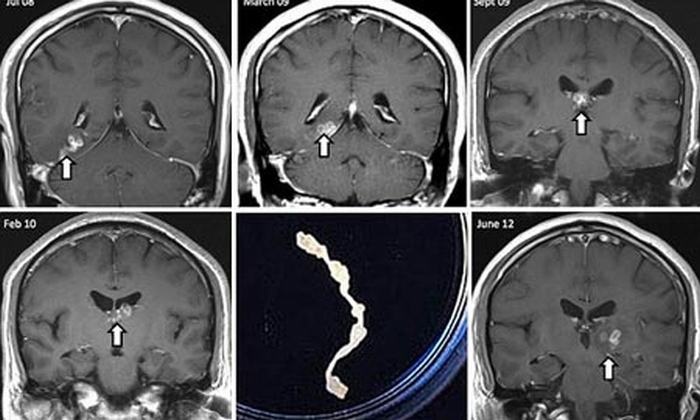

Sau khi ấu trùng giun móc chó mèo xâm nhập qua da người, chúng gây ra vết sẩn đỏ, ngứa, thành mọng nước. Từ vài giờ đến 2, 3 ngày sẽ phát triển ra vùng da chung quanh thành một hay nhiều đường ngoằn ngoèo, gồ cao, rất ngứa, kéo dài với tốc độ từ vài mm đến vài cm mỗi ngày, để lại dấu hiệu đoạn đường ấu trùng đã di chuyển. Có thể có các bóng nước nhỏ nổi dọc theo đường hầm ấu trùng di chuyển, bị thâm nhiễm bạch cầu. Do rất ngứa nên bệnh nhân phải gãi nhiều, gây trầy xước da dẫn đến bị nhiễm khuẩn da sinh mủ... Trong da, ấu trùng giun có thể tồn tại nhiều tuần đến hàng tháng. Đặc biệt, ấu trùng giun có thể thoát ra thành mạch máu, lên phổi gây bệnh ở phổi. Điển hình là hội chứng Loeffler với biểu hiện ho giống như bệnh lao, bệnh nhân ho khan, đau ngực, bạch cầu ái toan tăng cao. Chụp Xquang có hình ảnh thâm nhiễm giống lao nhưng hình ảnh này tự biến mất sau từ 1 - 2 tuần mà không cần điều trị gì.

Việc chẩn đoán bệnh phải dựa vào triệu chứng lâm sàng tại chỗ trên da và dấu hiệu dị ứng toàn thân. Xét nghiệm sinh thiết da cho thấy những u hạt chứa nhiều tế bào bạch cầu đa nhân ái toan có thể gặp được ấu trùng nằm giữa u hạt.